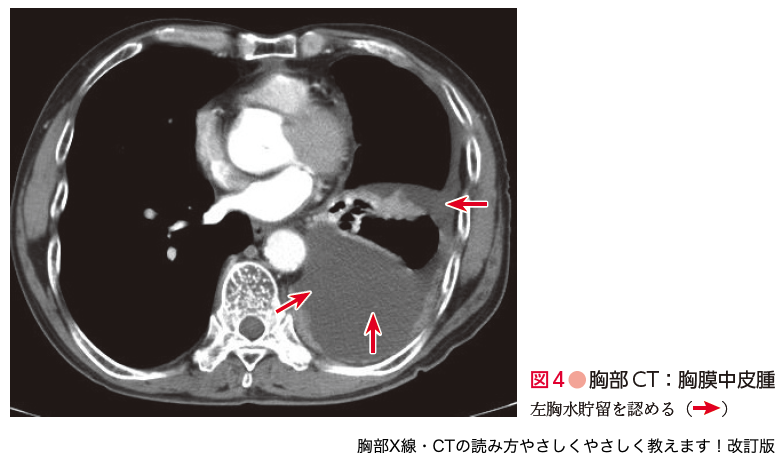

胸部CT道場36・飛び飛びに白くなる陰影32・結節影・腫瘤影3, 胸部X線・CTの読み方やさしくやさしく教えます!改訂版 - 羊土社「胸部のCT」村田 喜代史 / 上甲 剛 / 村山 貞之定価: ¥ 15000#村田喜代史 #村田_喜代史 #上甲剛 #上甲_剛 #村山貞之 #村山_貞之 #本 #自然/医療・薬学・健康書き込み等はありません。やさしい皮弁。申し訳ありませんが値下げはできませんので予めご了承ください。心臓血管外科手術 虎の巻 *裁断済み。(まとめ買いいただく場合には値下げを検討させていただきます。衛生化学詳解 上 第3版 京都廣川書店。)

胸部X線・CTの読み方やさしくやさしく教えます!改訂版 - 羊土社「胸部のCT」村田 喜代史 / 上甲 剛 / 村山 貞之定価: ¥ 15000#村田喜代史 #村田_喜代史 #上甲剛 #上甲_剛 #村山貞之 #村山_貞之 #本 #自然/医療・薬学・健康書き込み等はありません。やさしい皮弁。申し訳ありませんが値下げはできませんので予めご了承ください。心臓血管外科手術 虎の巻 *裁断済み。(まとめ買いいただく場合には値下げを検討させていただきます。衛生化学詳解 上 第3版 京都廣川書店。)